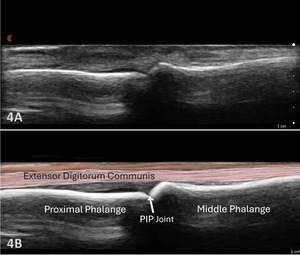

Examination Protocol Normal Sonographic Appearance

The extensor tendon can be examined in both long axis (LAX) and short axis (SAX) views. The tendons can each be seen at the MCP and PIP joints. The hyperechoic outline of the metacarpal and proximal phalanx will be seen at the MCP joint, while the proximal phalanx and middle phalanx will be visualized at the PIP joint. The extensor tendon will be an echogenic fibrillar structure in appearance. In the LAX view, the tendons will become smaller as they run more distally, making them slightly more difficult to visualize. In the SAX view, the tendon should be oval and fibular and should sit in the central position over the metacarpal. The soundhead may need to be toggled at the distal tendons’ insertion to avoid anisotropy. Dynamic visualization can be performed with resisted or active movement of the wrist or fingers.